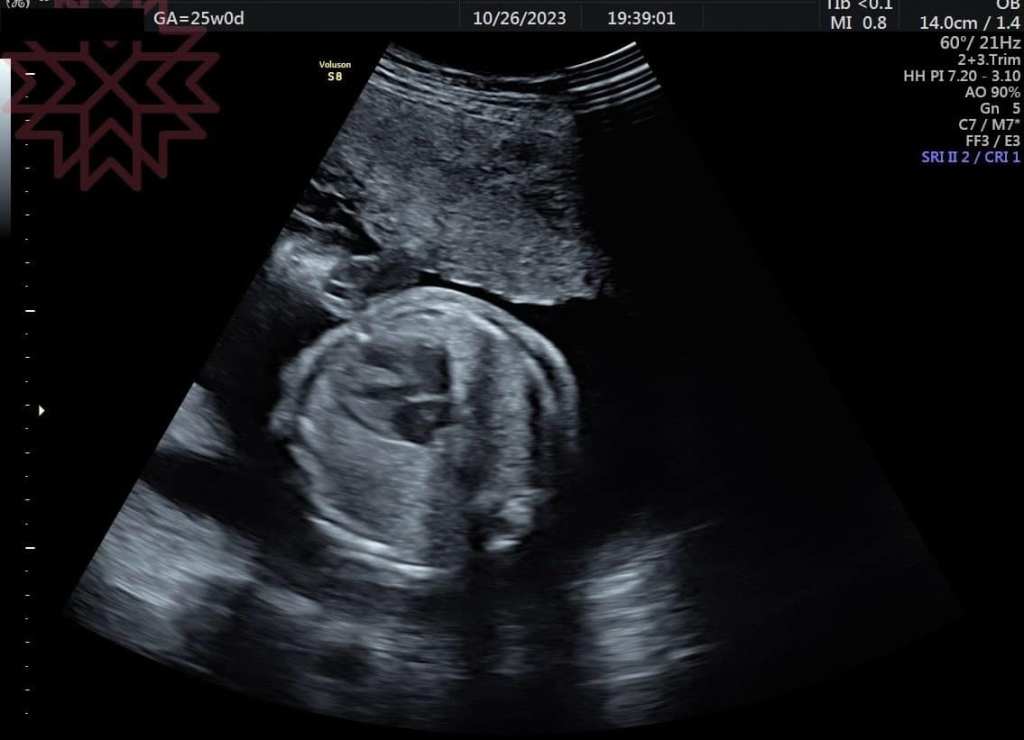

就是昨天晚上

超音波探頭一放上去

好了!!!

竟然自己好了!!!

(請看第二張影像

(就算看不懂的跟第一張比你應該也會知道